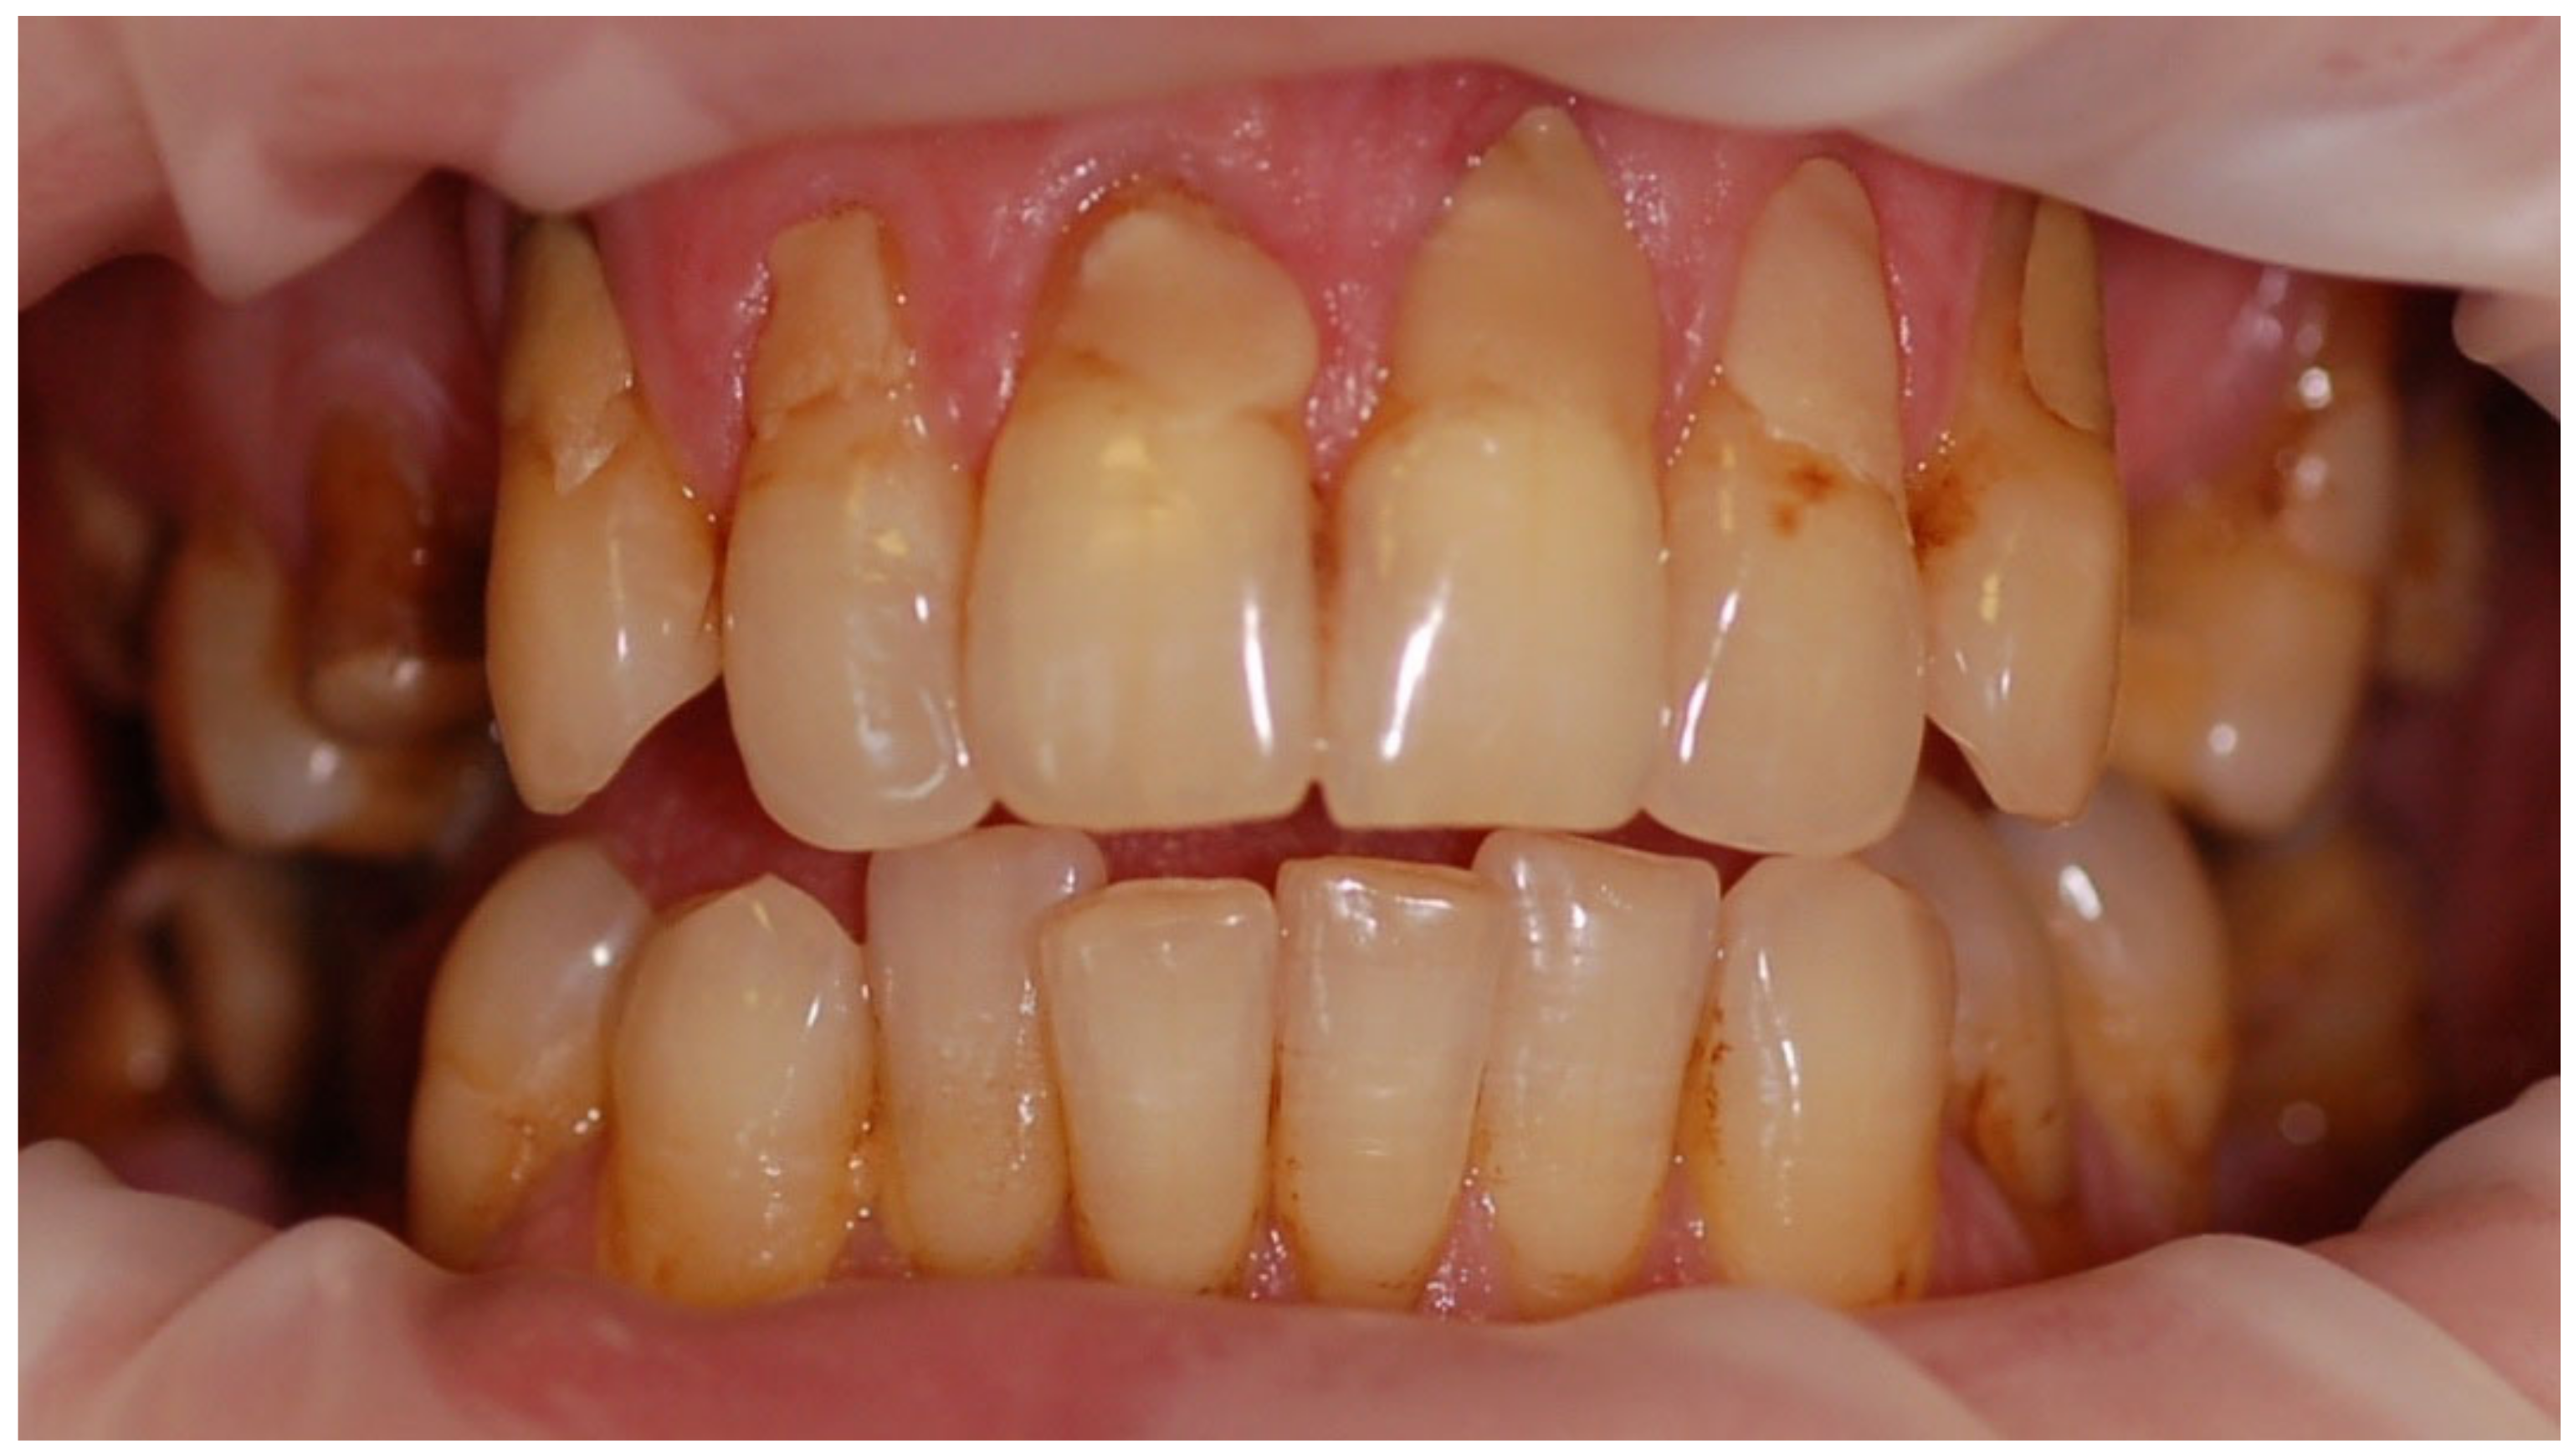

The mean API score among the subjects was 63.47% (SD = 22.78) and ranged between 22 and 100%. The mean value of the index for the control group was 68.75% (SD 21.46) and ranged from 19 to 100%. The p > 0.05, therefore the study and control groups did not differ significantly from the API value. The median value of the API index for the study group was 65 and 68.5 for the control group. Table 3 and Figure 1 present the API score and the API score pictured according to interpretation values. Figure 2, Figure 3 and Figure 4 show the clinical situation of the participants. The API values did not have a normal distribution in the analyzed groups (p < 0.05 from the Shapiro–Wilk test), so the analysis was carried out using the Mann–Whitney test.

Figure 4. Man, 42 y.o. API = 100%. The patient refused to use professional oral hygiene products and used soap to brush his teeth. Dental plaque deposits. Dental Biofilm-induced Gingivitis.

Ijerph 20 04792 g004